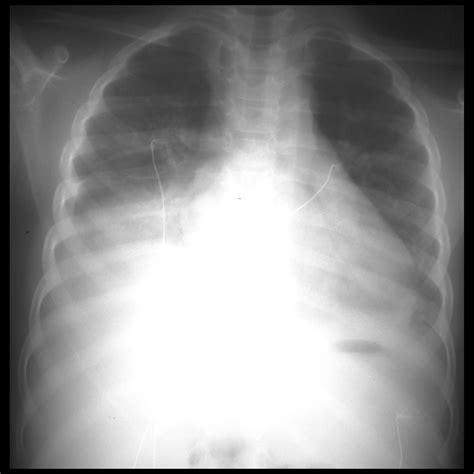

The Role of Diagnostic Imaging